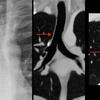

normal vessels

Date: 02/25/2013

Views: 3283

AP window

Views: 3134